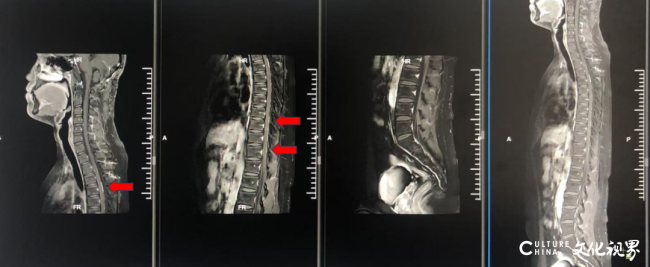

2024-10-21患者术后20月,MR全脊柱平扫+强化(颈胸腰):颈髓、胸髓及脊髓圆锥脊膜多发节段性强化,考虑脊膜转移。